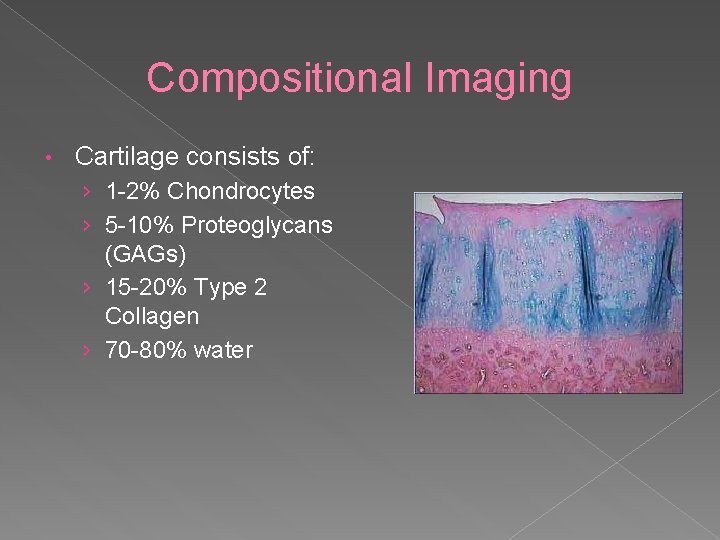

Compositional Imaging • Cartilage consists of: › 1 -2% Chondrocytes › 5 -10% Proteoglycans (GAGs) › 15 -20% Type 2 Collagen › 70 -80% water